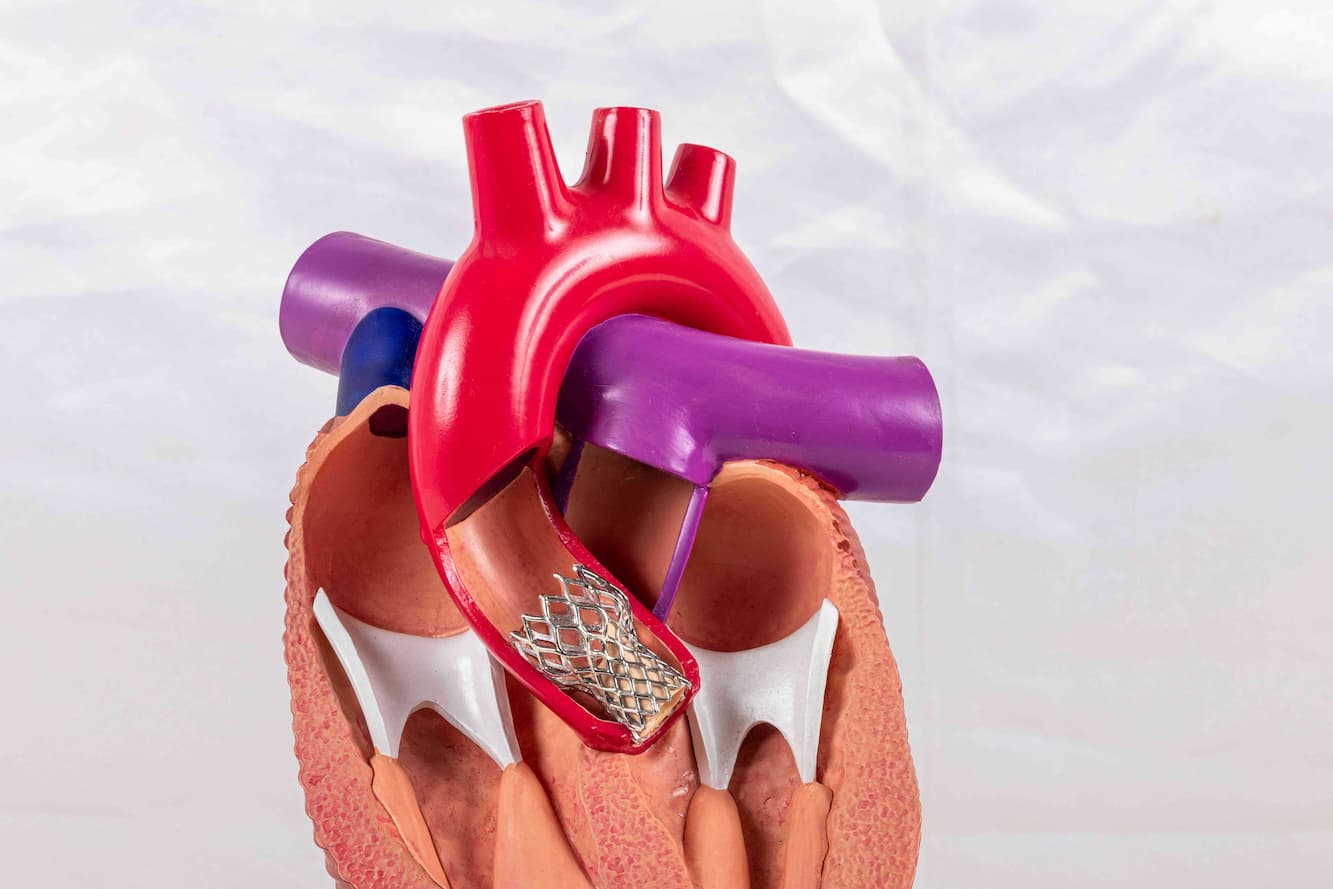

Cardiology plays a pivotal role in maintaining heart health, covering everything from regular check-ups to complex procedures. We partner with esteemed cardiologists from top hospitals.

Cardiology plays a pivotal role in maintaining heart health, covering everything from regular check-ups to complex procedures. We partner with esteemed cardiologists from top hospitals.